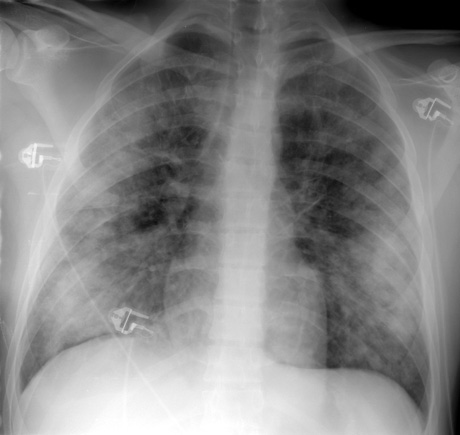

The patient shown below presented with chest pain and shortness of breath. The CXR revealed coarsened, prominent lung markings with a predominantly subpleural right pneumothorax. (Click image to enlarge)

CT was performed and demonstrated multiple cysts throughout the lungs. The pneumothorax was noted to be loculated and predominantly in the lower portion of the right hemithorax.